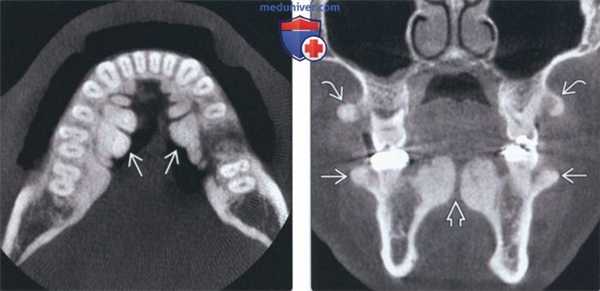

(Слева) На аксиальной КЛКТ визуализируются большие фестончатые рентгеноконтрастные разрастания, представляющие собой нижнечелюстные валики.

(Справа) На корональной КЛКТ определяется сдавление языка огромными нижнечелюстными валиками. Валики покрыты тонкой слизистой оболочкой, которая может травмироваться. При хроническом воспалении или нарушении функции валики удаляются. Обратите внимание на верхне и нижнечелюстные щечные экзостозы, которые часто сочетаются с нижнечелюстными валиками.